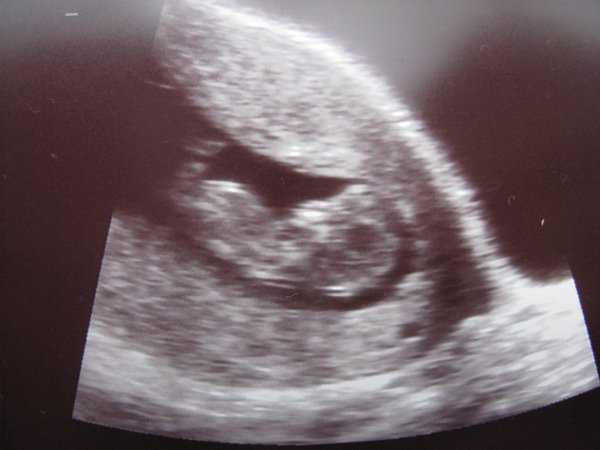

És a lényeg: minden okéééééééééééééééééééés!!!! 4 cm-nek mérték és így szerintük nem 9+6 hanem 10+5 vagyok ma, hááát nem tudom. Bejelentkeztem az integráltra otthon, 13+6-ig lehet megcsinálni, ha igaz az új számítás akkor 13+3 naposan tudok menni, határeset. De lehet hogy otthon megnézik rendesen és visszaminősítenek. Azért addig javítom a vonalzóm az újra, új szülési dátum január 1. Integetett, mozgott keze-lába, nagyon édes volt!!!! ÓÓÓÓÓÓÓÓÓÓÓÓÓ lányok most már én is hivatalosan is közétek tartozom, olyan boldog vagyok :lol: :lol: :lol:

Felrakom a képet is, remélem kivehető, kis feje, pocija, meg a lába látszik, bár nem túl jól. Kép

dejóóó nyufóóóó, akkor az uj időszámitásod szeint egyidősek vagyunk, meg nlzs-vel is egy nap hiján. hát ez nagyszerű! a képed is nagyon jó, cuki kis búra!!

nyufó a babád nagyon édes! Tényleg nagyon nagynak tűnik az én felvételemhez képest (9+2), szóval bizti sokkal előrébb jársz :) Gratulálok!

jaj de jó nyufó :) :) én tudtam h nincs baj,és olyan édesen látszik a kis formája :) :)

nyufó: jajj de jó, gratulálok. jó nagy a babócád... :-) gondolom most már tényleg megnyugodtál.

nyufó: nagyon gratulálok az UH képedhez, nagyon szép:)) És tök jó, hogy már előrébb is jársz, mint amire te számítottál:)

Nyufó: ez a bébi annyi de annyira édes!!! Szerdán már én is 10+3 leszek, remélem ugyan ilyen óriásbébiket fogok látni :wink: